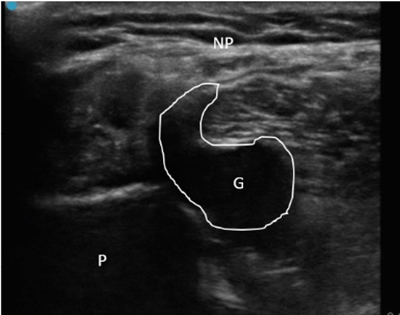

Neuropatía peronea secundaria a ganglión extraneural: revisión de literatura y propuesta de tratamiento. Caso no positivo

Peroneal neuropathy caused by an extraneural ganglion: literary review and treatment proposal. A non-positive case

Un enfoque diagnóstico correcto y un abordaje terapéutico precoz habrían supuesto una mayor mejoría clínica e incluso una recuperación neurológica completa del paciente. Por ello, este caso sirve para resaltar: a) el valor de la ecografía en neuropatías periféricas como herramienta diagnóstica y pronóstica y el de la ecografía en gangliones como arma diagnóstico-terapéutica; b) el uso de las pruebas diagnósticas como apoyo a una exploración física exhaustiva, y no como diagnóstico en sí mismas, y c) la importancia de la publicación de casos no positivos para optimizar recursos, evitar repetir errores, reducir el sesgo de publicación y facilitar el inicio de proyectos de investigación.

Figura 2